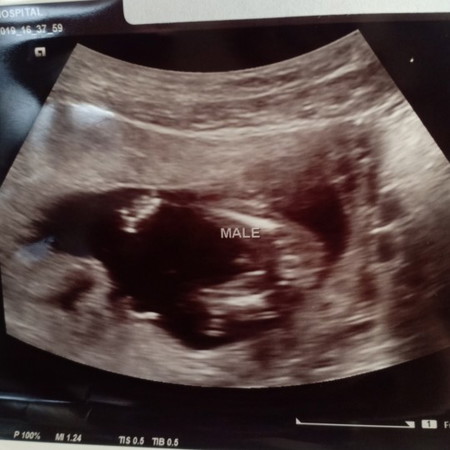

ตอนแรกหมอบอก ผช ไปๆมาๆไม่แน่ใจ เผื่อจะเป็นผู้หญิงก็ได้ ซาวด์ตอน16+1วีคค่ะหมอบอก รออายุครรภ์เยอะกว่านี้ มาดูอีกทีน่ะ อิแม่อยากได้ ผญ ค่ะ ได้ ผช แล้ว2คน ??อิแม่ก็ดูไม่ค่อยเป็นด้วยค่ะ ท้องที่ผ่านๆมาน้องไม่ให้เห็นเลยค่ะ เลยไม่แน่ว่า ผช รึ ผญ ค่ะ

อ่านจากคำอันตร้าซาวด์เป็นเมล ผู้ชายจ้าแม่

ช.ค่ะ หมอขึ้น maleให้แล้ว

Male บักหำน้อยเลยจ้า

ชายจร้าโด่ชัดเลย